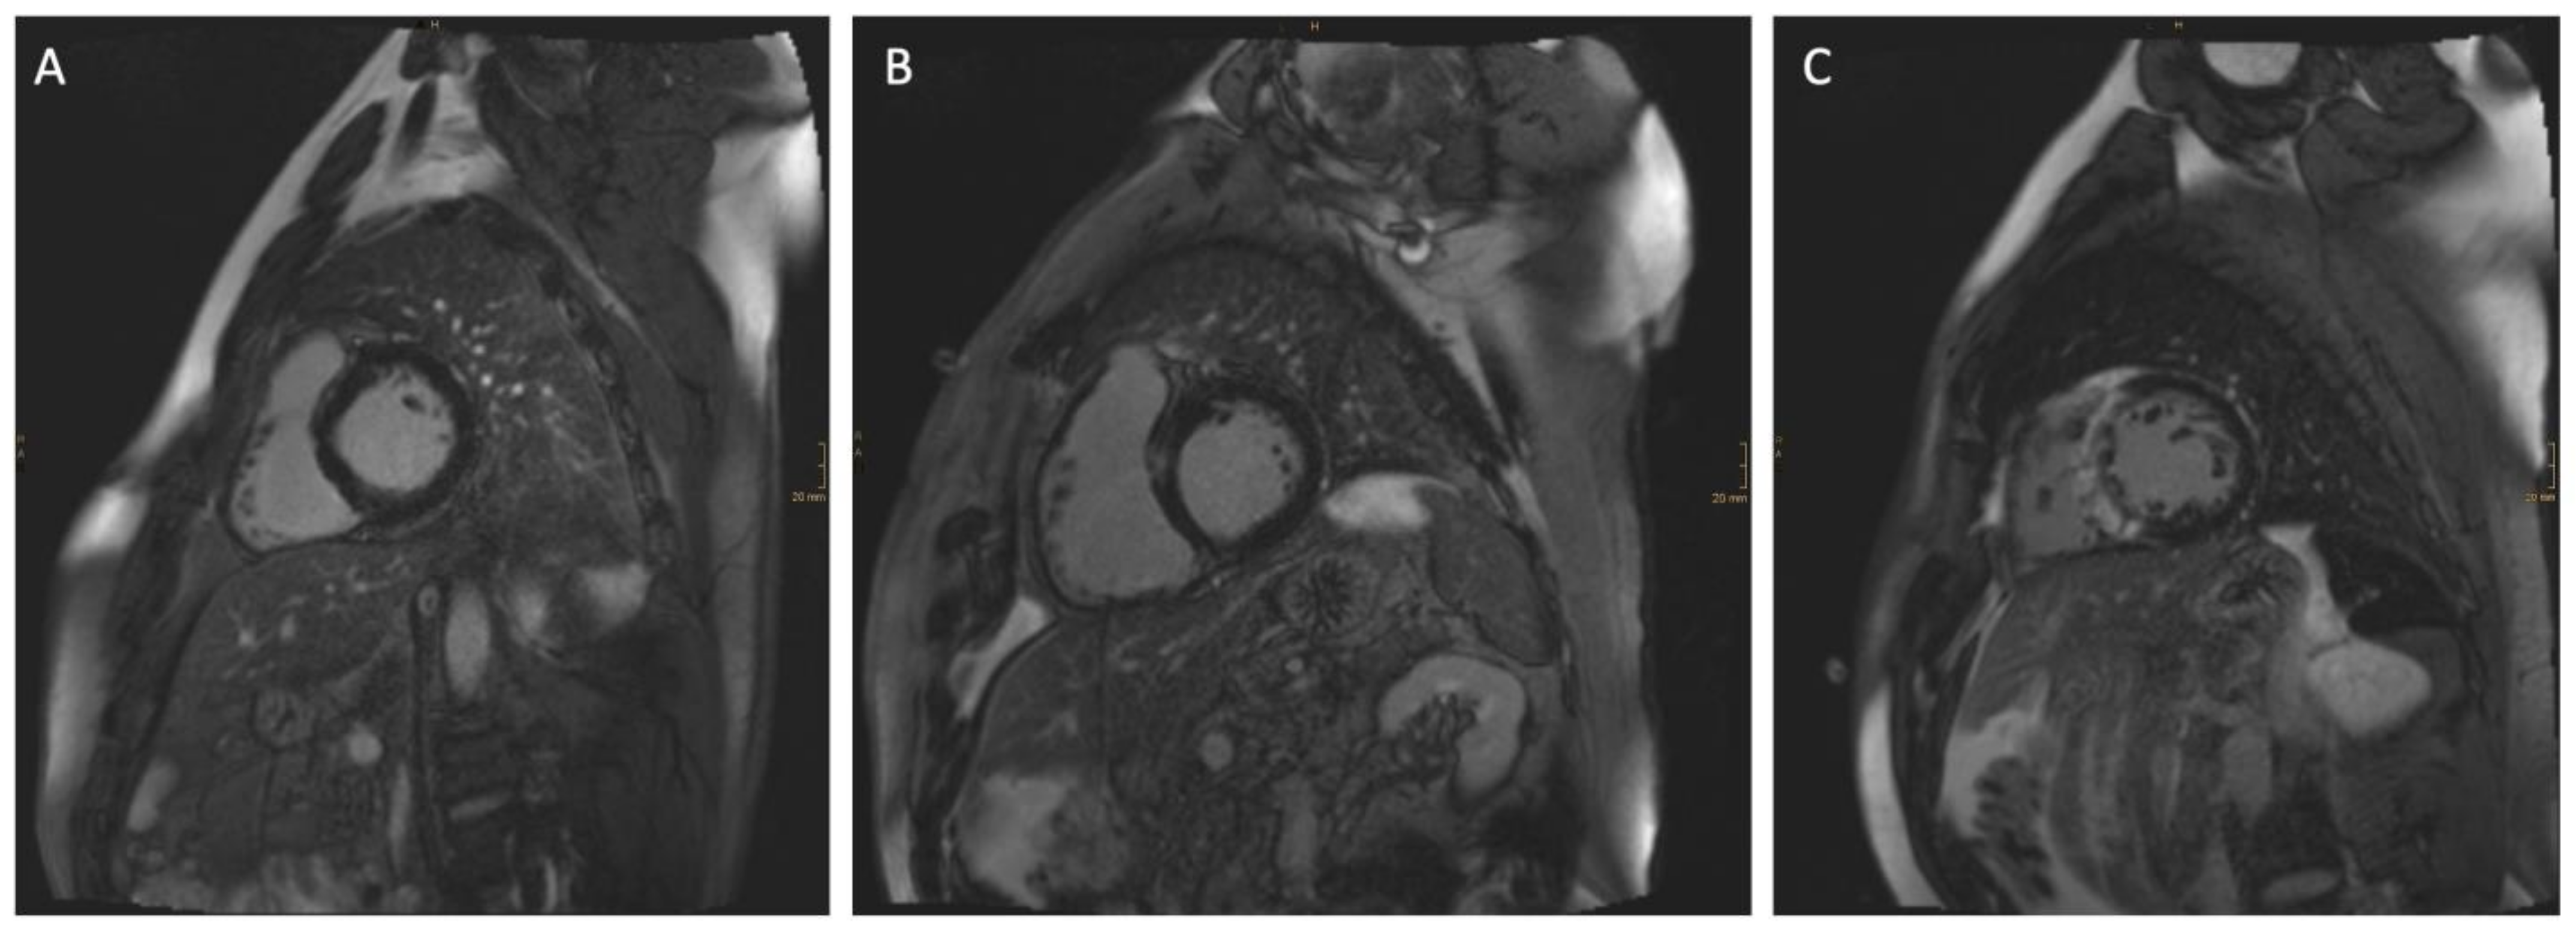

2.4. Cardiac Magnetic Resonance Imaging